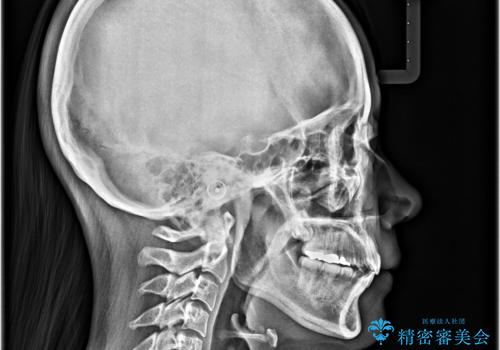

- 下の前歯のデコボコと、口元の突出感を改善したいと来院された患者様です。

突出感の強い上顎前歯をしっかりと後方移動させるため、上顎の裏側の補助装置(リンガルアーチ)とアンカースクリューを併用しています。

上下左右の第一小臼歯を抜歯して、目立ちにくいワイヤー装置で矯正を行いました。

上下の保定用マウスピースの他に、デコボコの強かった下顎前歯にはワイヤーで保定をしています。